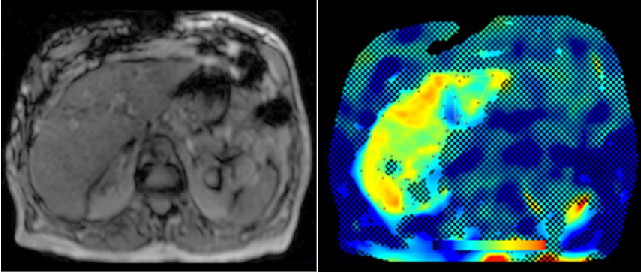

a) MRI for the evaluation of diffuse liver disease:

evaluation of different MRI methods (relaxometry, chemical shift imaging, multi-echo approach, Dixon screening), in order to detect diffuse liver disease (fat, iron or combined disease); influence of iron on the evaluation of liver fat.

b) MR-Elastography (MRE)

MRE is increasingly used in hepatic MRI to detect and classify fibrosis in the early stages before morphological changes have occurred. In our department, MRE is already integrated into the routine hepatic MRI protocol and used for various research projects.